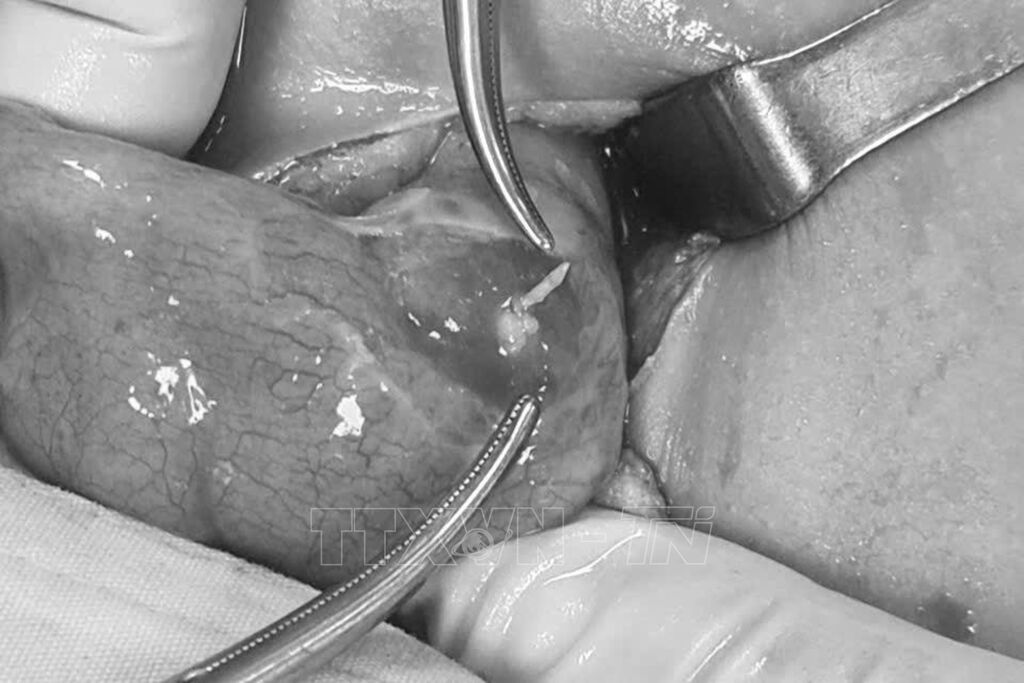

Theo bác sĩ chuyên khoa 2 Chung Tấn Định, trong quá trình phẫu thuật, các bác sĩ ghi nhận một dị vật kích thước khoảng 4cm, nghi là xương cá xuyên thủng manh tràng. Sau khi được phẫu thuật thành công, sức khỏe cháu Q đã ổn định.